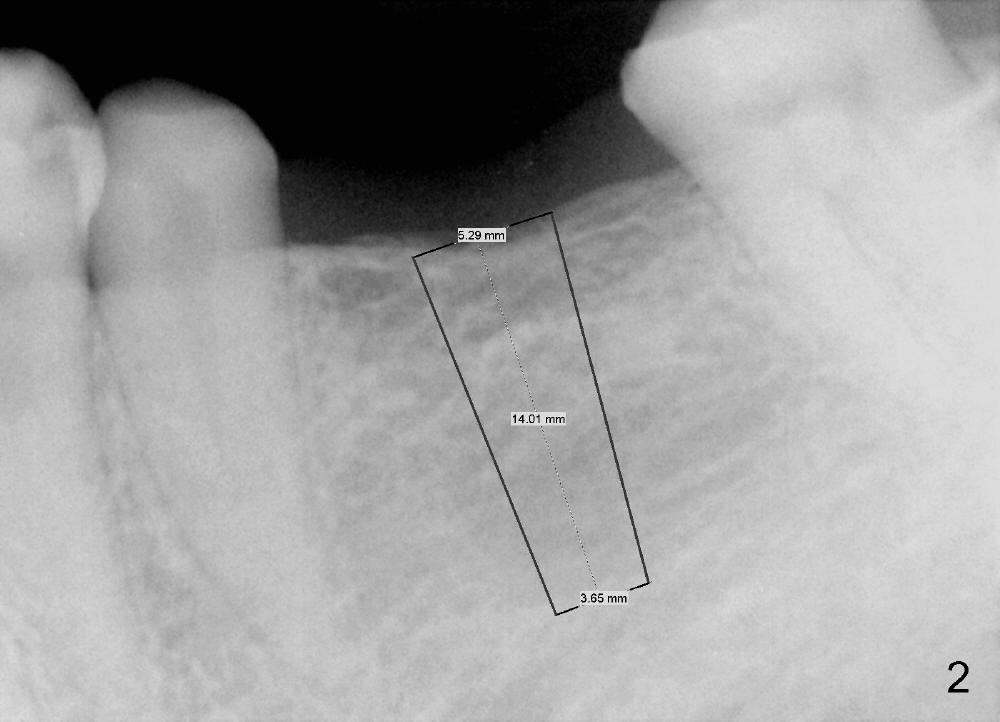

A 47-year-old man has lost a lower left fixed partial denture (FPD) for a while (Fig.1,2).  There is limited space between the abutments (of the teeth #18 and 20) and the opposing dentition.  The edentulous ridge is wide enough to use a 4 mm tissue punch.  A 5.3x14 mm bone-level implant is to be placed (Fig.2).  The base of the implant is at the level of the apices of the neighboring teeth.  As compared to Fig.1 in term of the Inferior Alveolar Canal (yellow line), there should be enough safe margin.  The first intraop PA is taken after 2 mm pilot drill for depth and trajectory check,  Drill stops are to be used for safety.  If primary stability is achieved, an abutment is placed and a provisional bridge will be fabricated to prevent further narrowing of the interocclusal clearance during 3-4 months of osteointegration.  How is outcome?